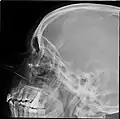

Paranasal sinuses radiograph (lateral)